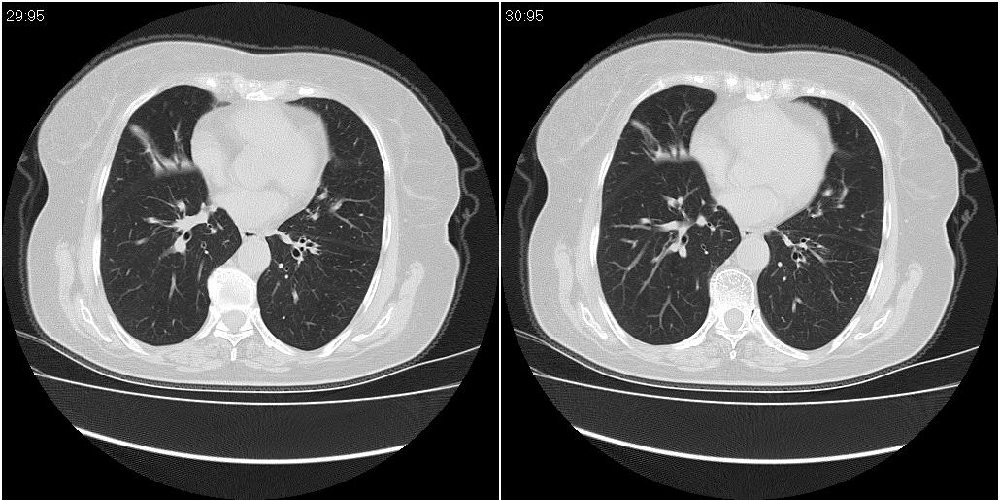

女性,72岁。去年9月份发现肺部病变,诊为肺结核并进行正规治疗至今,但复查后发现ct表现几乎没有变化。

右中间段支气管局限性狭窄,右中叶支气管亦稍显狭窄,但并未见明显占位表现,半年多了,无变化也许是好事,可能为炎性狭窄,建议继续随访。

双肺继发型tb并右中叶内膜tb,轻度支扩,左下胸膜肥厚粘连。

双肺继发性肺结核并右肺中叶节段性肺不张,左下胸膜肥厚粘连。

右肺中叶节段性肺不张,考虑结核或慢性炎症,建议做纤支镜检查。

双肺继发性肺结核并右肺中叶节段性肺不张